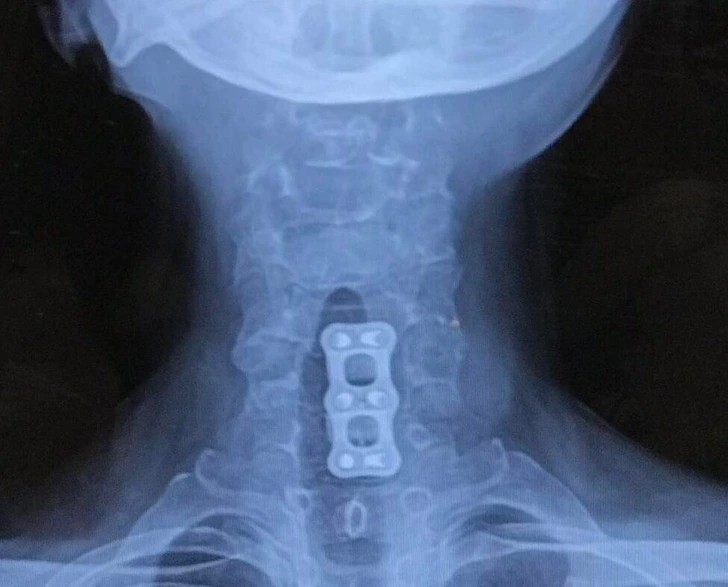

1. "Tytanowa blaszka, którą wstawili mi w szyję, wygląda trochę jak zawleczka puszki."

"Tytanowa blaszka, którą wstawili mi w szyję, wygląda trochę jak zawleczka puszki." © Dabo57 / reddit